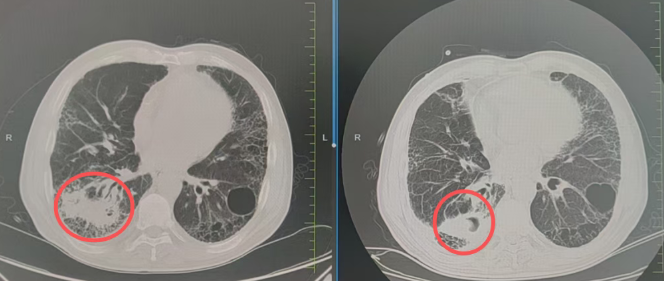

接诊后,张主任带领病区医疗护理团队立即启动紧急救治流程,通过多学科联合会诊(MDT),结合患者病史、影像资料与身体状态,精准定位出血病灶,全面评估治疗风险。针对患者病情,团队果断依托医院核心优势——国际前沿的放疗设备与技术体系,制定个体化精准放疗方案,直击病灶根源。

经过规范、系统的精准放疗,困扰患者许久的咯血症状完全消失,睡眠、饮食逐步恢复正常,精神状态好转。复查结果显示,肿瘤病灶缩小,各项生命指标平稳。